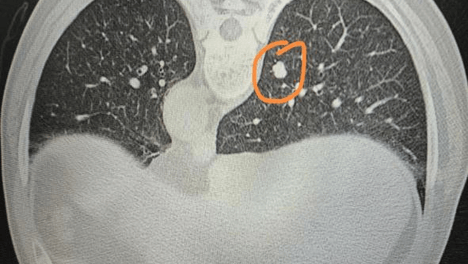

精准穿刺破困局!北京老年医院呼吸内科成功完成肺部微小结节诊断术

近日,北京老年医院呼吸内科刘前桂主任医师带领呼吸内科团队,在放射科密切配合下,成功为一名68岁的肺部微小结节患者实施CT引导下肺结节穿刺术。科室还邀请国内著名专家定期来医院查房,诊治疑难病例,指导危重症患者的…